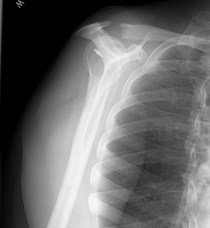

The Shoulder Knows

The bones warn me

Joints throb they swell

They ache they burn.